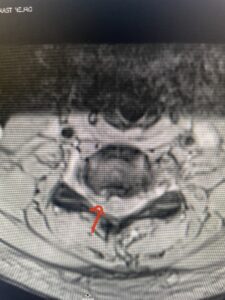

Fig 2a Sagittal and axial T2 weighted cervical MRIs demonstrating large C4 5 herniated disc with spinal cord compression red arrows

This 47-year-old male who four months prior was lifting weights developed sharp pain in his neck. After that he developed progressive numbness in his arms, neck pain and headache. He said that the right arm was worse than the left. On examination the patient had long tract weakness on the right side which included his triceps, finger extensors, hip flexors, and dorsiflexors. The patient did not have hyperreflexia. MRI (Fig. 2) demonstrated a massive, extruded disc herniation with severe cord compression. The patient because of progressive myelopathy and spinal cord compression was indicated for anterior cervical discectomy and fusion at C4-5 (Fig. 3). Patient had significant improvement of weakness and numbness post operatively.

Fig: 2b Axial T2-weighted cervical MRI demonstrating spinal cord compression from C4-5 herniated disc (red arrow)